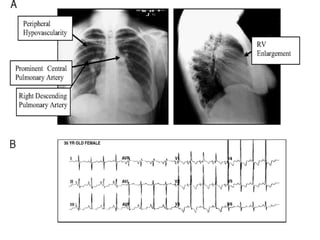

Diagnostico de HAP

• PAPm > 25 mmHg

• PWP < 15 mmHg

• RVP > 3 U W